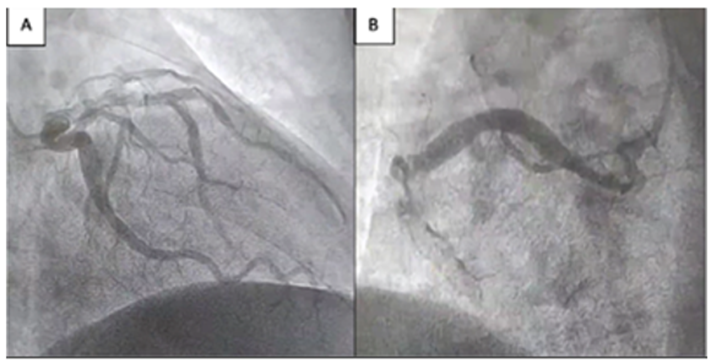

A right radial approach was used to perform the CA using a 5-Fr Tiger catheter (Terumo Corporation, Tokyo, Japan). The left main coronary artery ostium was cannulated, revealing a large-caliber, with out significant lesions; an ectatic left anterior descending artery (LAD), and a circumflex artery (CX) both also with out significant lesions . The right coronary artery (RCA) was then cannulated, revealing a large-caliber ectatic vessel (>6 mm) with thrombotic occlusion at the midsegment (Figure 1). Given the clinical picture, it was decided to proceed with PPCI to the RCA.

Figure 1: A. Left coronary artery without significatt lesions -Ectatic vessels. B. Largw-caliber ectatic coronary artery with acute thrombotic occlusion.